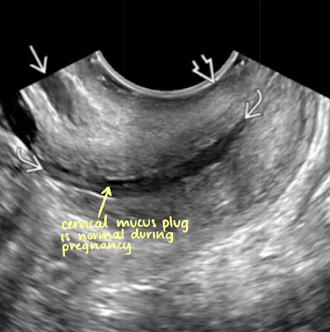

SONO: cervical cerclage

post-cerclage procedure; imaged transvaginally

cerclage stitches are echogenic with posterior shadowing

serial scans may be done to ensure cerclage remains secure and cervix is closed

what are the arrows pointing to?

cervical cerclage stitches